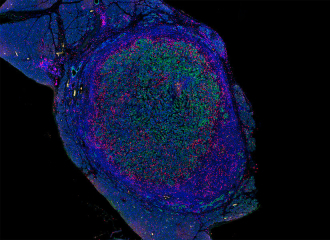

接受治疗后胰腺肿瘤中的T细胞(粉色)浸润了肿瘤细胞(绿色)图片来源:原文